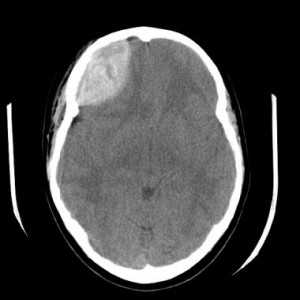

Кровоизлияние в мозжечок является следствием гипертонии и составляет около 10% всех случаев кровоизлияний в мозг. Обширное кровоизлияние может вызвать обструкцию 4 желудочка и гидроцефалию. Ранняя диагностика обычно осуществляется с помощью КТ. При МРТ головного мозга уже на вторые - третьи сутки кровь становится гипоинтенсивной на Т2-зависимых МРТ за счет превращения оксигемоглобина в дезоксигемоглобин. Эритроциты остаются неразрушенными. Дезоксигемоглобин на Т1-зависимых МРТ изоинтенсивен белому веществу. Процесс изменения гемоглобина идет снаружи внутрь, поэтому внутримозговое кровоизлияние имеет кольцевую структуру. На Т2-зависимых МРТ снаружи идет широкая зона гиперинтенсивного отека, в центре - резко гипоинтенсивное кольцо внутриэритроцитарного дезоксигемоглобина. Уже на 5-6 сутки дезоксигемоглобин превращается в метгемоглобин, который гиперинтенсивен на МРТ обоих типов зависимости.

КТ головного мозга. Кровоизлияние в мозжечок.